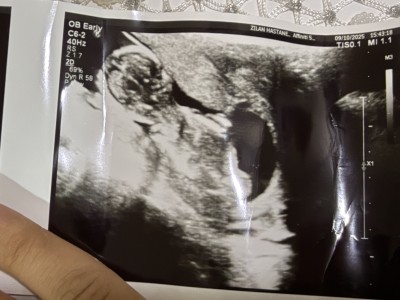

Merhaba arkadaşlar 15 haftalık oldum ama bebek kendini göstermiyor cinsiyeti çok merak ediyorum tahmin eder misiniz 🫶

Gebelik haftası 15

Canım bebeğin kız görürsün iki çizgi var hem kızlar kendini kapatıp gizler

Canım kıza benzettim ben de 15 haftalığım gecen gittim Dr erkeğe benzettim dedi 2 3 hafta sonra netleşir dedi ben de onu bekliyorum heyecanla sağlıkla gelsin inşallah ❤️

Yapısı narin kız gibi . Allah gönlüne göre versin inşallah